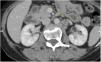

Contrast and non-contrast computed tomography (CT) of the abdomen and pelvis, with axial views and multiplanar reformation, were carried out (Fig. 1).

The CT scans identified small bowel segments distended with air and neutral fluid. There was homogeneously enhanced concentric wall thickening (with no stratification pattern) up to 21mm thick at the level of the distal ileum, which conditioned a narrowing of approximately 70% of the lumen, causing retrograde dilation of the ileum. Air and residual material were observed in the colon.

The thickening of the distal ileum walls ended with a retrograde obstructive defect and suspicious data of hepatic and para-aortic retroperitoneal lymph node metastatic activity, suggesting a carcinoid tumor. Exploratory laparotomy revealed a small bowel tumor at 210cm from the angle of Treitz and 160cm from the ileocecal valve that obstructed 80% of the intestinal lumen, causing wall thickening up to 10cm. Intestinal resection with a 10cm proximal and distal extension of healthy tissue was performed, along with an end-to-end intestinal anastomosis. Liver examination identified smooth edges and no superficial or deep tumors were palpated. Given the absence of bulges or macroscopic alterations, retroperitoneal exploration was not performed.